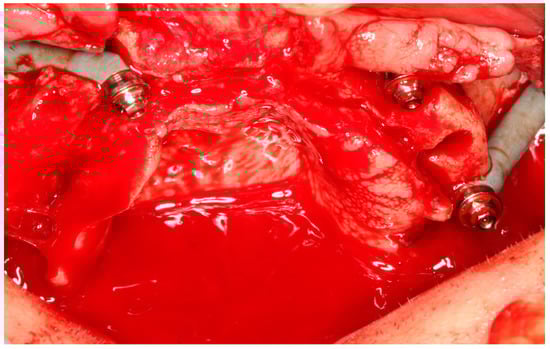

2.5.1. Subperiosteal Implants

Surgical Technique